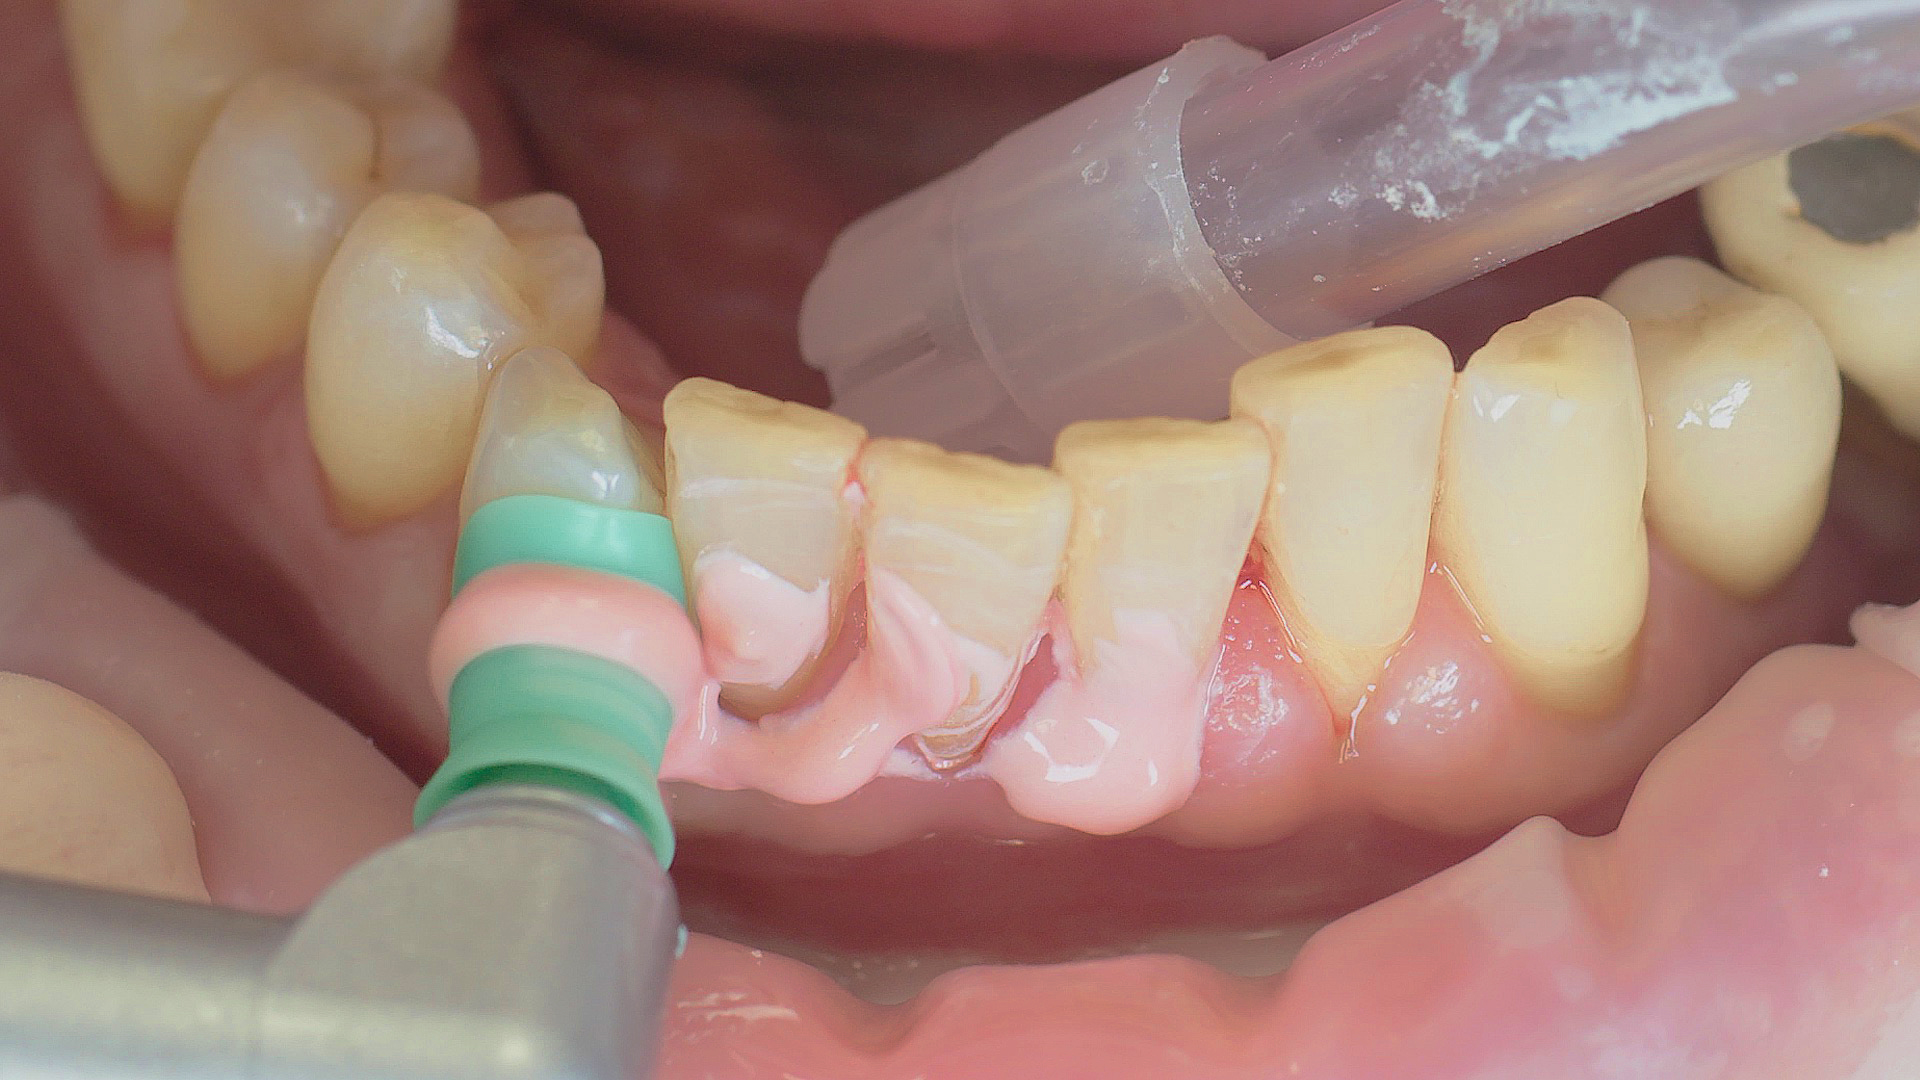

Fig. 2). Le recours en complément à la thérapie photodynamique, à l’aéropolissage ou aux antibiotiques locaux et systémiques n’est pas suffisamment documenté (Pr Dr Sema Hakki).[4] D’après le Dr Sergio Bizzarro, un diagnostic amélioré des biomarqueurs peut conduire à une utilisation plus fréquente des thérapies personnalisées à l’avenir.

Un détartreur à air réalise un détartrage initial efficace, une étape du traitement parodontal initial.

Fig. 2 : Un détartreur à air réalise un détartrage initial efficace, une étape du traitement parodontal initial.